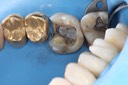

Russ Tabata #30 pre-op

Russ Tabata #30 amalgam removal

Russ Tabata #30 prep